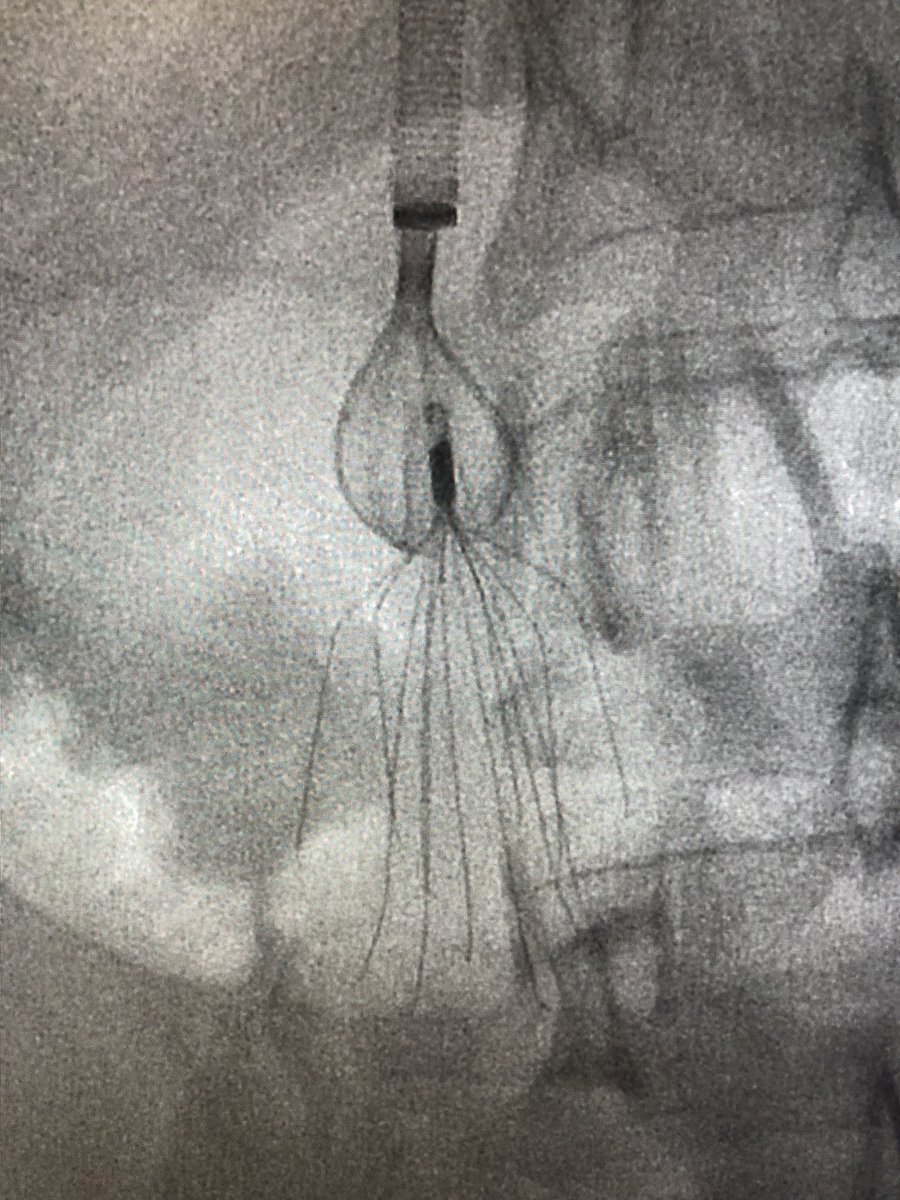

8 year-old Bard Meridian #filterOUT. Surrendered to Avantec’s Captus device. @rkryu @kush_r_desai @NorthwesternIR #iRad #GTFO

UCD_IR's tweet image. 8 year-old Bard Meridian #filterOUT. Surrendered to Avantec’s Captus device. @rkryu @kush_r_desai @NorthwesternIR #iRad #GTFO